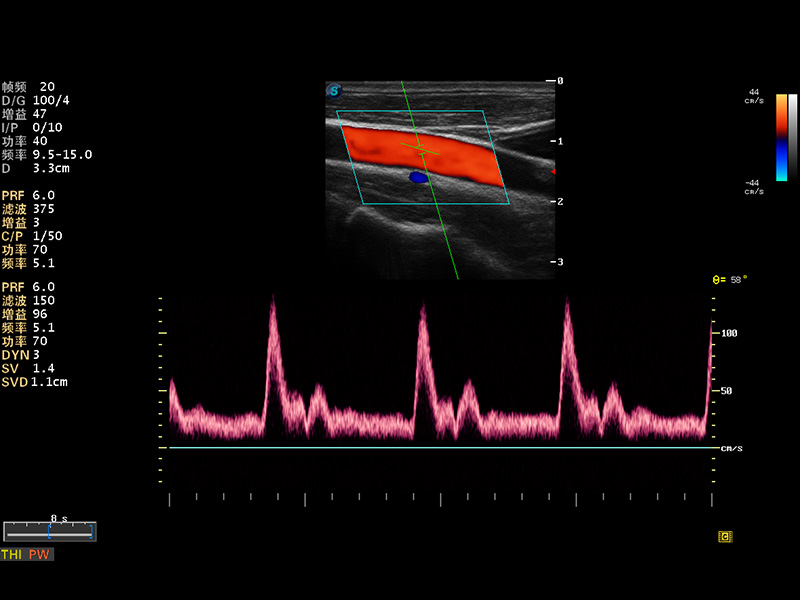

S8 EXP便携式彩色多普勒超声诊断仪是1xBET研发的高端全身应用型便携彩超。高通道的VIS平台融合可视化(Visual)、智能化(Intelligent)和人性化(Smart)的特点,配以1xBET自主研发生产的探头大家族,使您能够快速、准确的获得病人信息,提高工作效率的同时减轻疲劳。

成像技术

多波束形成器

μ-Scan微米成像

谐波成像